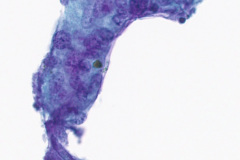

Cytologic Diagnosis: Negative for malignant cells, acute inflammation, multinucleated giant cells, few poorly formed granulomas, iron pill fragments.

Cytology:

Initial diagnosis of IPA is not always readily distinguishable on cytology examination of slides. There may be a presence of a small amount of yellow-brown material on modified Romanowsky and Papanicolaou stains which without the clinical history of aspiration could easily be interpreted as non-specific artifact or other types of pigmented particles such as hemosiderin or carbonaceous particles.6 Histological examination of biopsy material is typically the gold standard for diagnosis, wherein iron pill injury is characterized by the presence of crystalline iron fibrils in the presence of necrosis or in an ulcer base.1 An iron stain such as Perls’ Prussian Blue can aid in determining the iron composition of the yellow-brown material by staining iron as a bright blue color.9 Microscopic features of the biological response to the aspiration exposure may include the presence of multinucleated giant cells, hemosiderin-laden macrophages, granulomas, and reactive atypia of squamous metaplasia. Care should be taken when assessing the Prussian Blue stain results as the hemosiderin in macrophages will also stain positively.9